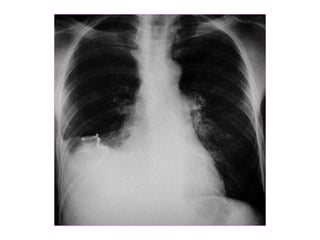

Chest x ray

Finally, Check theLung Fields • Infiltrates • Increased interstitial markings • Masses • Absence of normal margins • Air bronchograms • Increased vascularity